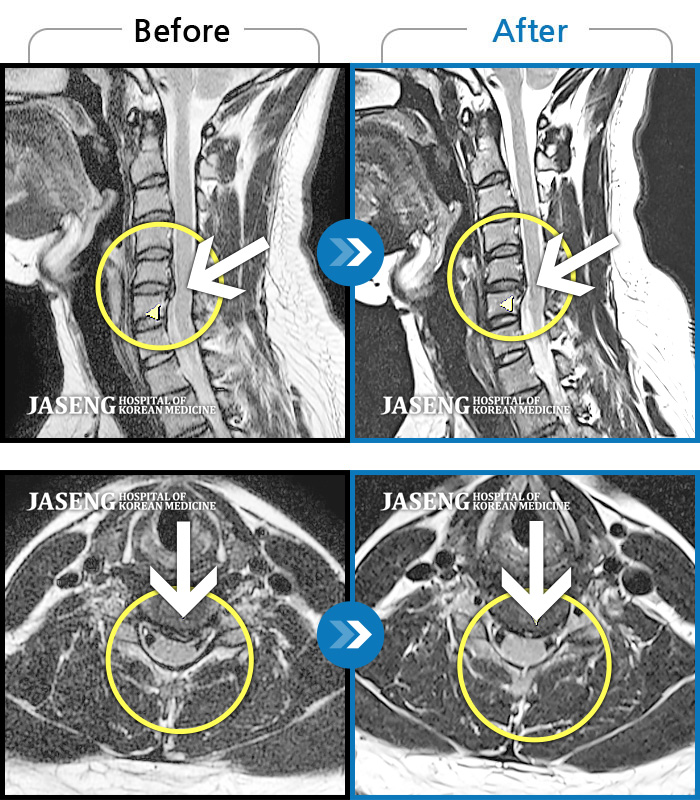

목디스크

광주 · 장영우 원장

후경부 양측부터 승모근까지 묵직한 통증, 좌측 상지 수지까지 이어지는 저린감

촬영시기

2121.04.27 ~ 2121.12.11

2021.12.17